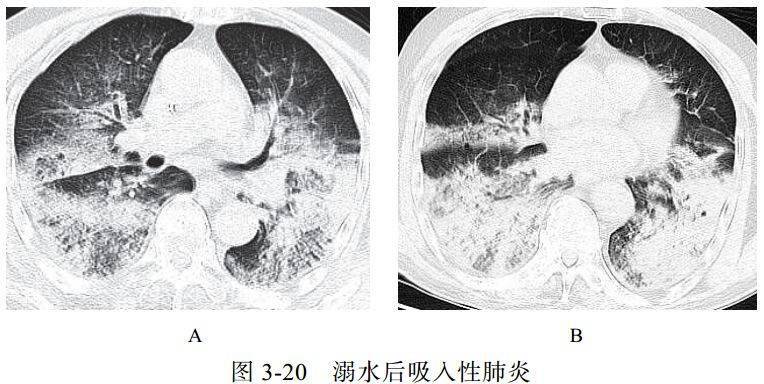

(六)吸入性肺炎

吸入性肺炎常见于慢性衰弱性疾病、咽和食管结构异常、全身麻醉等患者。吸入性肺炎可导致肺损伤或肺部炎症性疾病,如肺内节段性肺炎、支气管肺炎、肺脓肿和脓胸等。老年人存在隐性误吸

影像学表现:无明显特异性特征,需结合病史与临床表现来做出诊断(图 3-20)